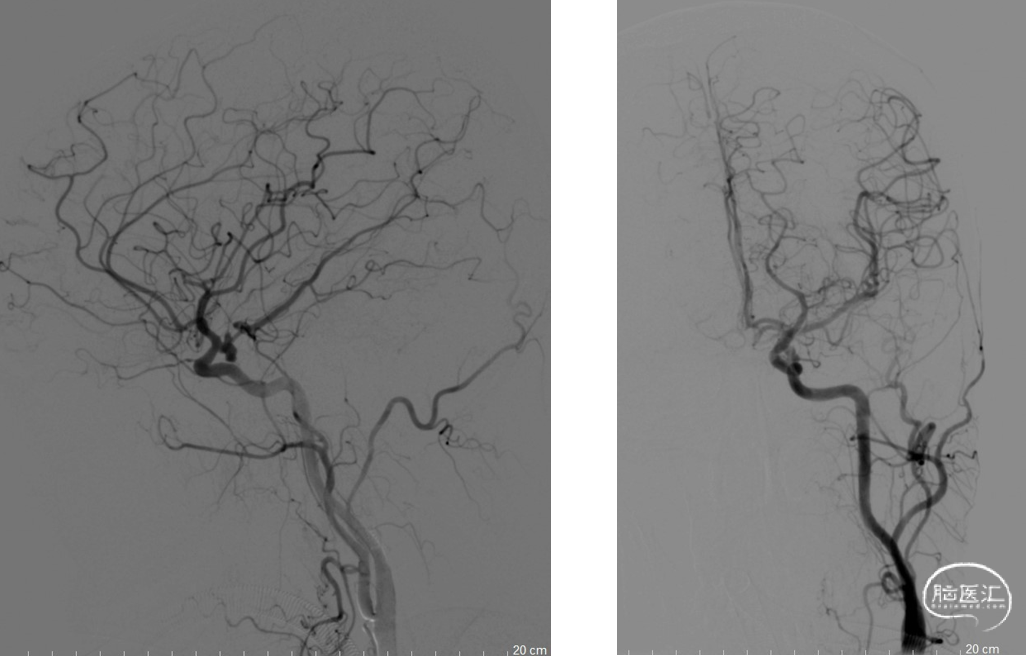

左侧颈总动脉正侧位造影

右侧颈内动脉正侧位造影

左侧颈内动脉后交通段动脉瘤整体大小约4.9mm×9.3mm,

子瘤约4.3mm×2.4mm,

主瘤体5.8mm×4.1mm,

瘤颈宽3.0mm,不规则

在Synchro0.014 200mm微导丝携带下将Excrlsior SL-10微导管置于左侧大脑中动脉M1远端,在Synchro-0.014 200cm微导丝携带下将两根Echelon-10微导管塑形后送至瘤腔内

分别将1.5mm*4cm弹簧圈送入子瘤,主瘤体送入6mm*20cm,5mm*15cm,1.5mm*4cm弹簧圈(EV3),沿SL-10微导管将4mmx21mm支架(Neuroform Atlas)置入左侧颈内动脉至左侧大脑中动脉

复查造影动脉瘤少量充盈,继续将3枚1mm*3cm弹簧圈(EV3)沿子瘤的Echelon-10微导管送入。复查造影示左侧颈内动脉、左大脑中动脉、大脑前动脉、左侧后交通动脉显影良好,动脉瘤栓塞完全。